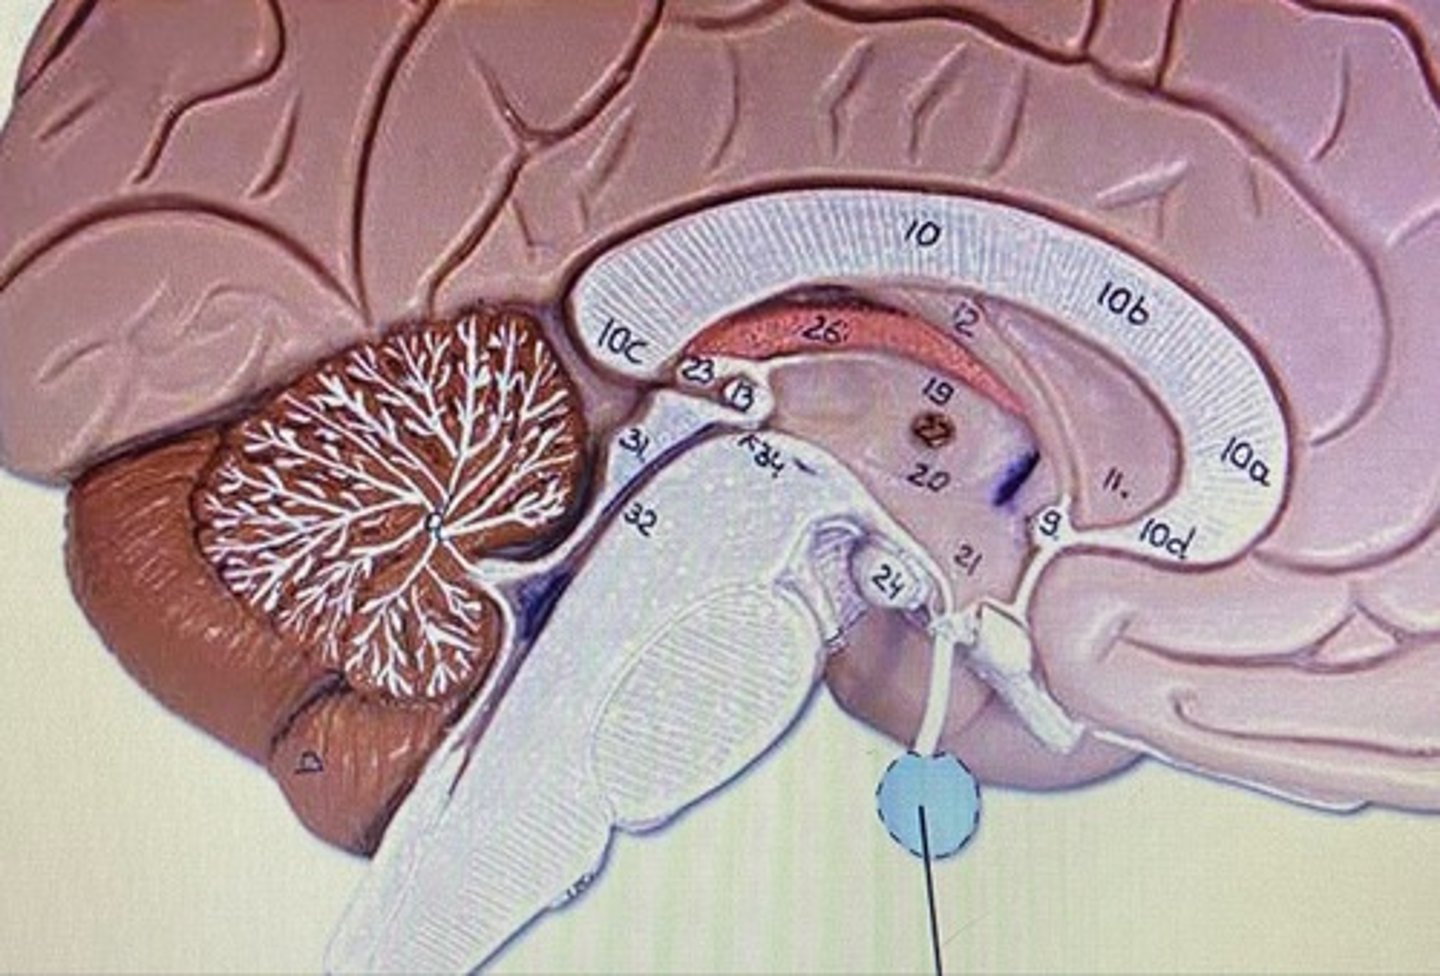

Frontal Lobe

Parietal Lobe

Temporal Lobe

Occipital Lobe

Cerebrum

Cerebellum

Arbor Vitae

Medulla Oblongata

Pineal Body/Gland

Corpus Callosum

Choroid Plexus

Fornix

Thalamus

Hypothalamus

Infundibulum

Pituitary Gland

Olfactory Bulb

Olfactory Tract

Superior Colliculus

Inferior Colliculus

Lateral Ventricle

Third Ventricle

Fourth Ventricle

Cerebral Aqueduct

Cerebrum

-conscious brain

Cerebellum

-coordinates muscles movements, muscle memory

Transverse Fissure

-separates cerebrum & cerebellum

Pons

-bridge that links medulla oblongata to thalamus

Medulla Oblongata

-houses autonomic centers

Sheep Lateral Ventricle

-produces and contains cerebrospinal fluid

Sheep Fornix

Sheep Thalamus

-gateway to cerebral cortex

Sheep Hypothalamus

-located under the thalamus on human brain

-controls pituitary gland and autonomic centers of medulla oblongata